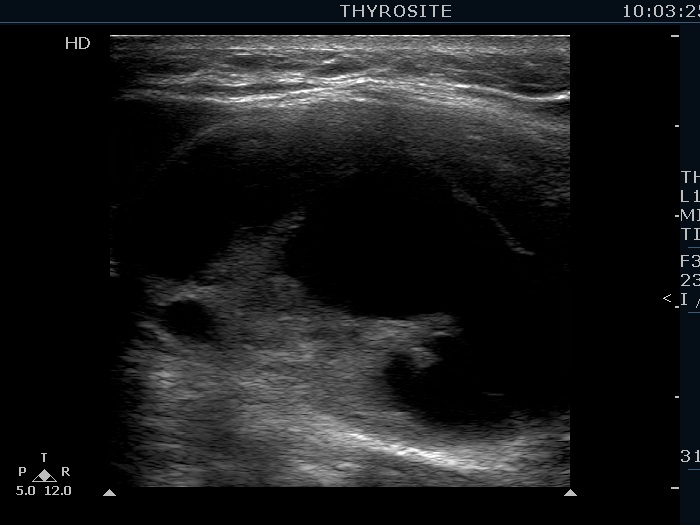

Elastography - case 2145 (ultrasonographic picture 3)

Right lobe, longitudinal scan. Compare the solid part located in the ventral and in the dorsal surface of the nodule. The latter is more echogenic because of the enhancement of the echo signal caused by the cystic fluid.